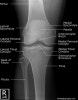

2. A/P Knee View

Demonstrates: femorotibial articulation

Helpful for: Knee Arthritis, Tibial Plateau Fracture, Distal Femur Fracture

Position: supine with cassette under knee and femoral condyles parell to cassette.

Beam directed to point 1-2cm distal to the patella.